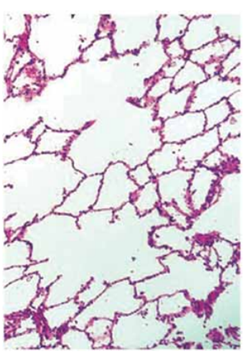

Analise a imagem a seguir.

(Junqueira & Carneiro, Histologia básica)

Assinale a alternativa que corretamente identifica o tecido visualizado.